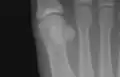

The first metatarsal. (Left.)

The first metatarsal bone is the bone in the foot just behind the big toe. The first metatarsal bone is the shortest of the metatarsal bones and by far the thickest and strongest of them.[1]

Like the four other metatarsals, it can be divided into three parts: base, body and head. The base is the part closest to the ankle and the head is closest to the big toe. The narrowed part in the middle is referred to as the body of the bone. The bone is somewhat flattened, giving it two sides: the plantar (towards the sole of the foot) and the dorsal side (the area facing upwards while standing).[1]

The head is large; on its plantar surface are two grooved facets on which the sesamoid bones glide; the facets are separated by a smooth elevation.